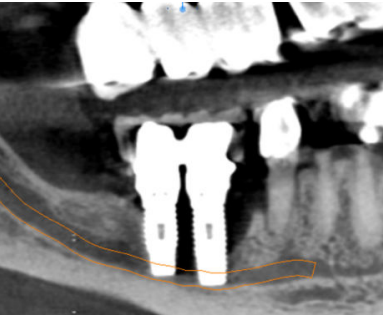

Cinco meses después, se efectuó un nuevo CBCT para evaluar la ganancia ósea conseguida. En el estudio tomográfico pudo observarse una ganancia media vertical de 6,4 mm y una ganancia media horizontal de 7,8 mm, lo que sumado al hueso remanente permitió colocar dos implantes Klockner® KL RP de 4 x 10 mm en 46 y 47 a 35 N/cm2 (Figuras 8-12). El diente 45 se decidió rehabilitar mediante un póntico en extensión para prevenir la lesión del nervio mentoniano durante la inserción de los implantes. La segunda fase se realizó a los tres meses de su colocación. Tras la cicatrización del tejido blando, se tomaron las impresiones mediante el escáner intraoral Carestream Dental CS 3600 y se realizaron las restauraciones protésicas finales con tecnología CAD/CAM (Figuras 13 y 14).